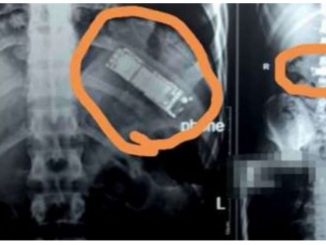

Telefon Bimbit Ditemui ‘Tert4nam’ Dalam Perut Lelaki, Dipercayai DiteIan 7 Bulan Lalu

Dipercayai melakukan pr4nk bersama rakan-rakan, seorang lelaki Mesir dipercayai telah meneIan telefon bimbit dan ia kekal di dalam perutnya selama tujuh bulan, lapor Gulf News. […]